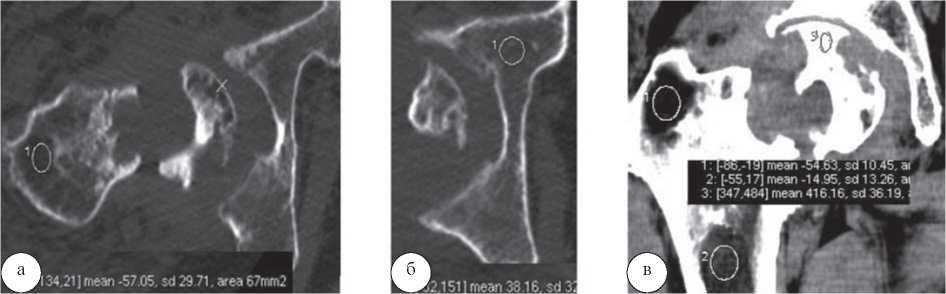

Результаты и их обсуждение. У больных хроническим остеомиелитом проксимального отдела бедренной кости в периоде обострения с преобладанием гнойного воспаления головка бедренной кости была почти полностью разрушена в 42 случаях. Фрагмент сохранившейся головки содержал структуры различной плотности: от 386,27±38,65 HU до 105,23±35,17 HU, а также зоны резорбции с отрицательной плотностью. Плотность крыши вертлужной впадины не превышала 56,16±11,63 HU, в сохранившихся участках головки субхондральный слой был истончен, плотность его составляла 285,37±46,21 HU. Плотность кости в области большого вертела находилась в отрицательном спектре шкалы Хаунсфилда (-57,05±29,71 HU), рисунок 1.

Рис. 1. МСКТ тазобедренного сустава больного Ц., 53 года. Аксиальные срезы (а, б). Выраженный остеопороз в области большого вертела (—57,05 HU), крыши вертлужной впадины (38,16 HU), неровные, «изъеденные» контуры фрагмента головки и сохранившейся части проксимального отдела бедренной кости MPR (в).